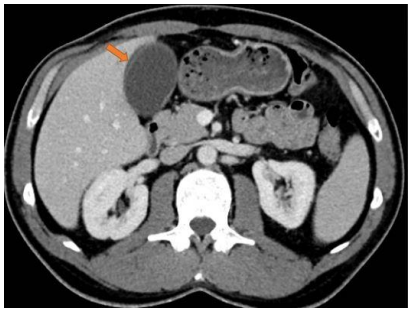

Observe o exame a seguir para responder as questões 39 e 40.

O método de imagem utilizado evidencia